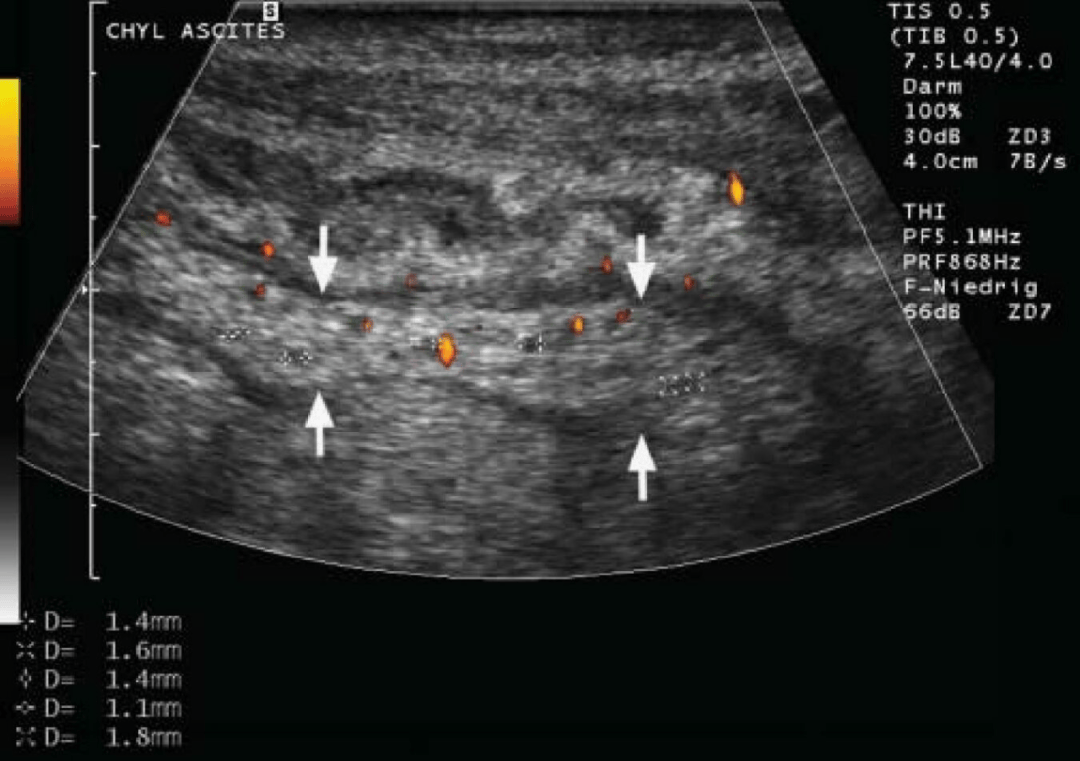

图3:扩张淋巴管。同病例1,超声显示在“白肠”(箭头所示)内可见多处细线状无回声区(测量标记处),为扩张的淋巴管。Hint:淋巴管扩张的形成机制与分枝杆菌阻塞淋巴回流、肠壁内乳糜微粒淤积有关。